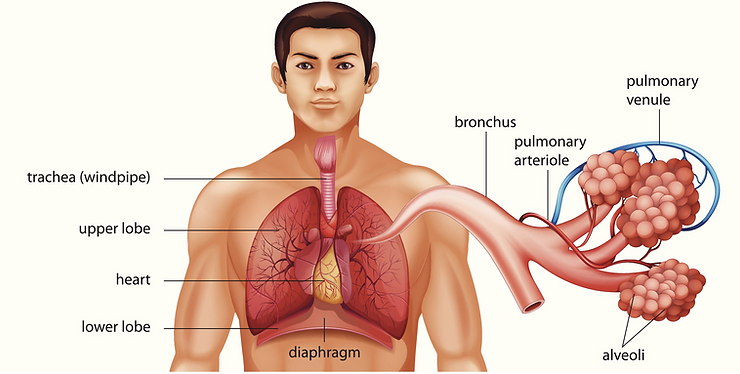

The alveolus of the lung (plural: alveoli, from Latin alveus, “little cavity”), is a tiny structure within the lungs measuring approximately 200 micrometers, or just a fraction of a centimeter. These tiny alveoli are bunched together in grape-like clusters to form alveolar sacs. On the surface of the alveoli are networks of tiny blood vessels called capillaries. It is through these tiny capillaries that airway oxygen from the air you inhale diffuses into the blood stream as a result of partial pressure. At the same time, carbon dioxide, the waste product of respiration, moves from the capillaries into the alveoli and out through the airways of the lungs where it is blown out with the next exhalation. [2]

When you are unable to inhale sufficient airway atmospheric oxygen (O2), or if your blood or body cells are incapable of transferring or using oxygen properly, you can become hypoxic, or low oxygen in your organs, glands and tissues, or hypoxemic, with oxygen in your red blood cells. These two conditions are caused by oxygen deprivation due to pathological blood coagulation which is extremely hazardous to your health if allowed to continue untreated. If you have COPD, interstitial lung disease or any another acute or chronic breathing condition like asthma, your body will not be able to absorb airway oxygen or diffuse sufficient amounts into your blood or tissues. Without oxygen delivery to your body cells that make up your organs, glands and tissues the normal cell function is compromised and your health will be at serious risk.[3]

One of the purposes of the red blood cells is to remove highly toxic and acidic cellular metabolic waste in the form of carbon dioxide and lactic acid and to pick up oxygen for delivery to cells for normal functioning. The process is called cellular respiration or oxygenation which takes place in the alveolar sacs of the lungs.

In order for the red blood cells to remove acidic metabolic waste and to pick up life giving oxygen they must pass through the pulmonary vein and then into the capillary pools. If the red blood cells are in pathological coagulation or aggregation there is no way to enter. Why? Because the entry into the capillary venules that branch off from the pulmonary vein measure 3 to 5 microns (1 micron is 1/25,000 of an inch – See Micrograph 1) and a single red blood cell measures 7 microns which makes it impossible for the red blood cell to enter the capillary venules if they are aggregated or coagulated into groups of red blood cells! [4]

When red blood cells group or clot together into a fibrin net, a clotting protein created when there is injury to the cell membrane and/or endothelial cells that protect the lining of blood vessels, (See Picture 2) the red blood cells cannot enter into the pulmonary vein and then into the capillary pools to release their acidic carbon dioxide waste and pick up oxygen in the alveolus of the lungs. (See Illustration 1)[5]

Pathological blood coagulation or disseminated intravascular blood coagulation (DIC) inside the pulmonary vein will prevent the free passage of red blood cells into the alveoli of the lungs via the pulmonary capillaries. {See Phase Contrast Micrograph 3 and 4) Erythrocytes or red blood cells must go into the pulmonary capillaries single file. If they cannot pass into the pulmonary capillaries of the lung to the alveoli this will cause oxygen deprivation that leads to red blood cell hypoxia (carbon dioxide poisoning) degeneration, genetic mutation, sepsis and sudden death.[6][7][8]